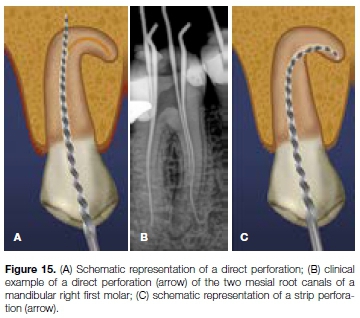

A direct perforation is a channel or communication between the root canal space and surrounding cementum (Figures 15a and 15b). Such a perforation can result in the destruction of cementum and the irritation and/or infection of the periodontal ligament in the surrounding area. As with ledging, perforation of curved canals is associated with stiff instruments with sharp cutting tips used in a rotational motion.

A perforation that occurs along the inner wall of a curved root canal is referred to as a "strip perforation" (Figure 15c).